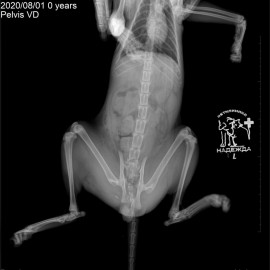

Котик Персик после покуса собаки. Обратились с жалобами на отсутствие опороспособности на левую переднюю и задние лапы. После рентгенографического исследования поставлен диагноз: вывих левого локтевого сустава, перелом костей правого крестцово-подвздошного сочленения, перелом лонной и седалищной костей таза. Проведена операция: остеосинтез левого локтевого сустава, остеосинтез правого крестцово-подвздошного сочленения таза.

Снимки 3-5 после операции